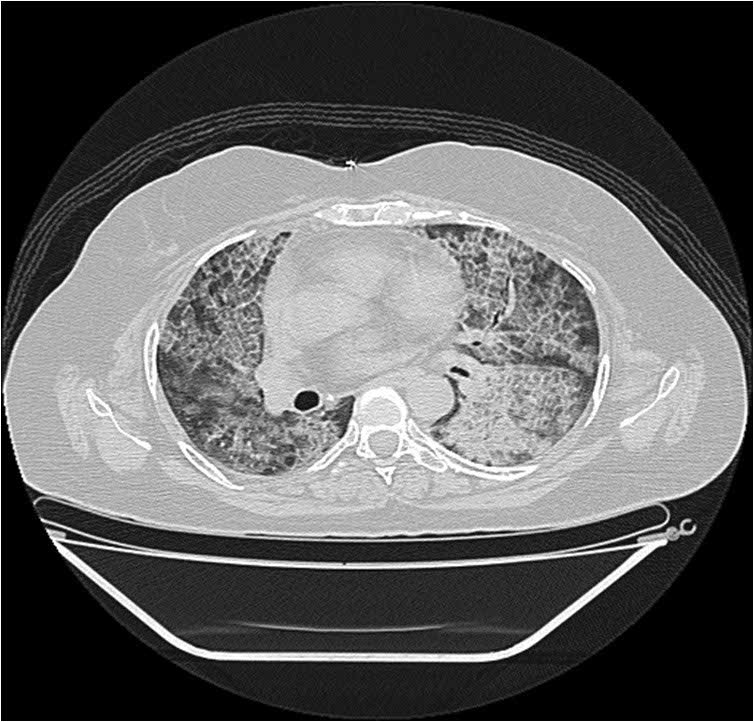

A 60-year-old lady suffering from a rare lung disorder ? Pulmonary alveolar proteinosis (PAP)? – has been recently treated successfully by the Pulmonology Department of KRIMS Hospital, Nagpur.

Pulmonary alveolar proteinosis is a rare lung disease. Its incidence rate is one case per 50 lakh people. It is caused due to the accumulation of abnormal protein material called surfactant? inside the lungs. This leads to reduced oxygen gas exchange inside the lungs which ultimately leads to severe breathlessness.

PAP is diagnosed through a variety of tests including x-rays, lung function test, CT scan and lung biopsy. Till today, there is no curative medicine which can reduce the protein deposition inside the lung. It is important to remove the protein from the lungs so that the patient can breathe normally. The process of removal of deposited protein from the lung is known as Whole Lung Lavage (WLL) and is the current standard treatment for PAP. This procedure is tedious and sometimes can be life threatening.

When the 60-year-old lady at KRIMS hospital went through a CT scan, the doctors were suspicious of PAP. On doing the open lung biopsy, she was proven to be a case of PAP. At the time of diagnosis, she was unable to maintain oxygen saturation and her lung functions were very low. The team of doctors from KRIMS Hospital including Pulmonologists, Anesthetists and Physiotherapists then planned to perform WLL on this patient.

A repeat lavage was performed on November 4, after a month. This time the right lung was lavaged while the left lung was mechanically ventilated. Approximately seven litres of water was instilled with a return of six and a half litres. The procedure took four hours to complete. There is drastic change in the patient’s health and CT scans now. She is now able to walk on her own without oxygen support and her quality of life has improved.